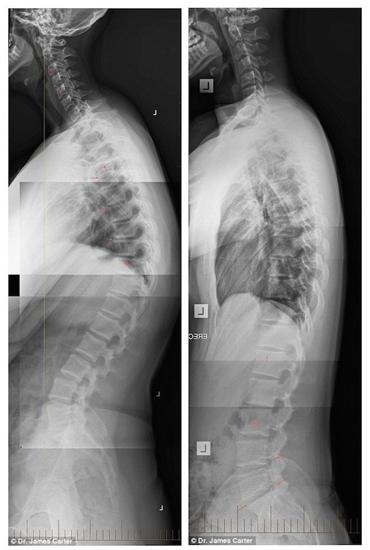

The following X-ray images taken by Dr. Carter give a look at how badly text neck is affecting children.

Shocking X-rays of teenagers have been released to raise awareness about the condition called “text neck”: pictured (left) is a 16-year-old girl who is developing a hunchback and (right) is a 17-year-old boy with an abnormally curved spine.